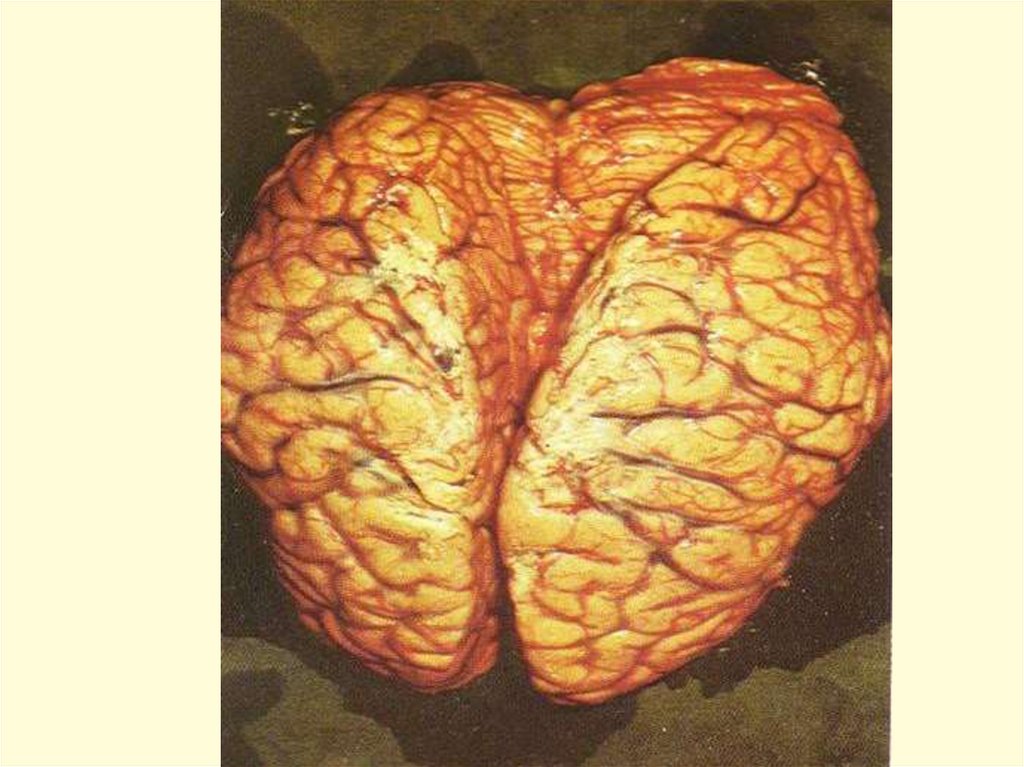

ПАТОМОРФОЛОГИЯ

– N.m. вызывают острую воспалительную

реакцию в месте внедрения.

Эндотоксемия приводит к диффузному

васкулиту и ДВС-синдрому,

Кровеносные сосуды заполняются сгустками

крови с большим содержанием фибрина и

лейкоцитов, что приводит к кровоизлияниям во

всех органах, но на коже они наиболее заметны

и часто сопровождаются некрозами в центре

крупных элементов.